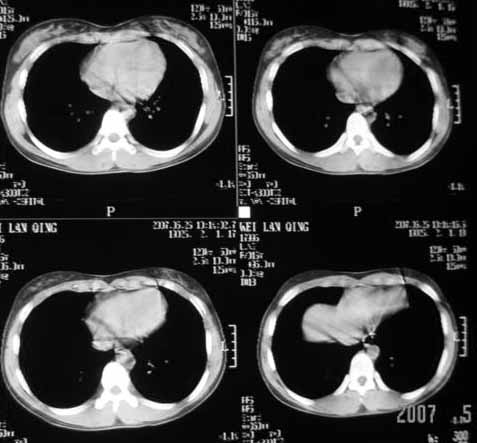

以下是引用dyqct在2007-5-26 12:01:00的发言:[br]右第二肋腋侧呈明显膨胀性、分叶状改变,内无明显间隔,ct值49hu,病变大小约67x57mm,周围硬化缘无断裂,内缘见多数骨嵴,肿块与正常骨间界限清楚。无移行带。周围软组织无浸蚀,胸膜腔无积液。[br]考虑:1、右第二肋动脉瘤样骨囊肿可能性大;[br] 2、需同骨巨细胞瘤、浆细胞瘤、骨纤鉴别。

[br]病灶定位在肋骨上,原因如图[br]定性支持邓老师的动脉瘤样骨囊肿、骨纤[br]巨细胞瘤较少发生钙化,所以我不考虑[br]桨细胞瘤不会发生膨胀性改变吧,经验少期待老师们的指正[br]骨结核内大多有沙粒状钙化,所以可能性也不大